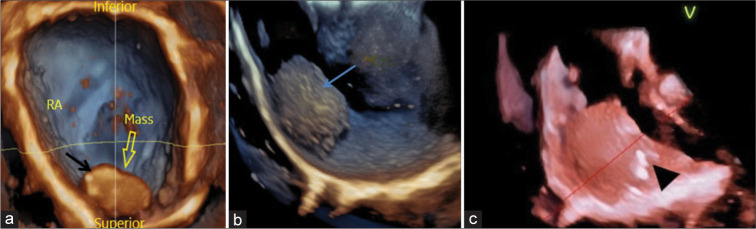

Cardiac masses are a significant cause of patient morbidity and mortality by virtue of their symptoms and surgical removal. Preoperative diagnosis of a cardiac mass is usually based on clinical correlation and transthoracic echocardiography findings. Myxomas are the most common benign cardiac tumors, commonly occurring in the left atrium attached to the interatrial septum near the fossa ovalis. Although, at times atypical location and unusual morphology may pose a diagnostic dilemma with 2D echocardiography. 3D echocardiography with its multifaceted advantages, including multiplanar cropping abilities and superior imaging quality can help distinguish between a clot and a myxoma.